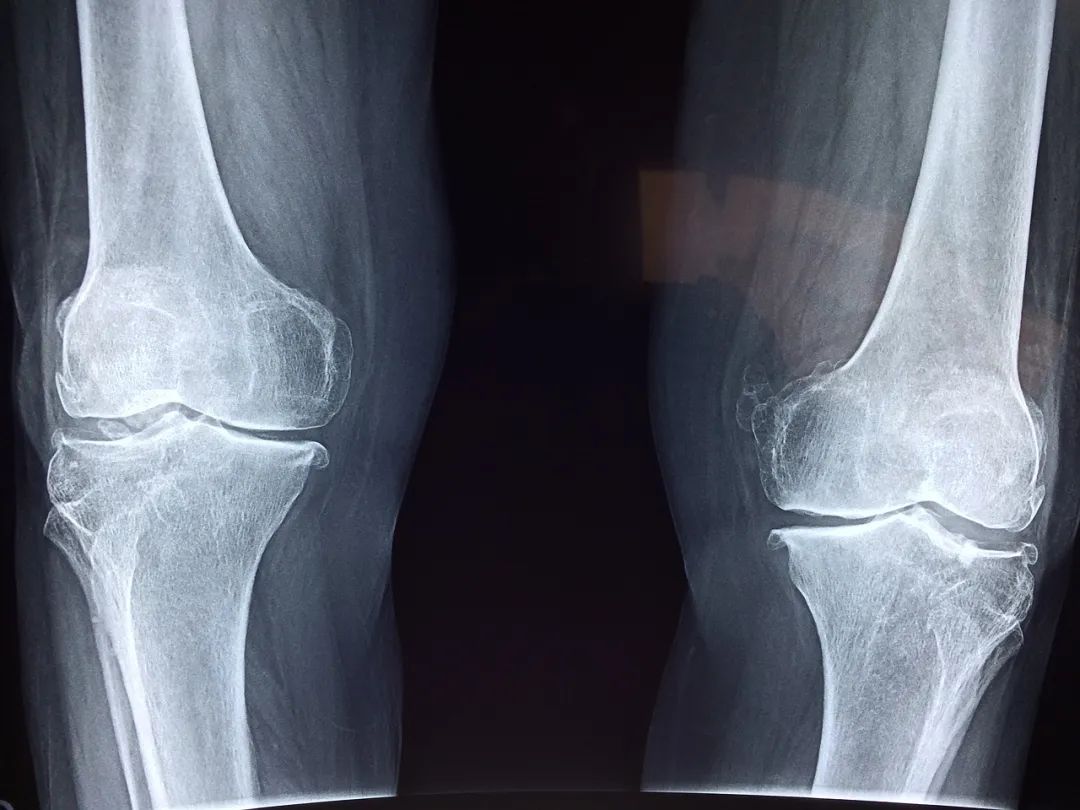

膝关节出现这些症状,可能已经提示关节受损

如果你根本想不起来自己的膝关节,首先表明它是健康的,当你开始关注你的膝关节,可能就表明它出现了一些问题。

那么我们膝关节常出现的问题大概有两类:

有的时候膝关节会出现一些响声,很清脆的一次弹响,不伴有疼痛的,可能是一些生理性的弹响,比如说我们滑膜增生等。如果退行性的骨关节病、关节炎,它的响声是非常有特征性的,就像冬天你去握一把雪,雪球就发出咯吱咯吱的声音,这种握雪感是非常典型的骨关节炎的一个表现,叫作骨摩擦音。